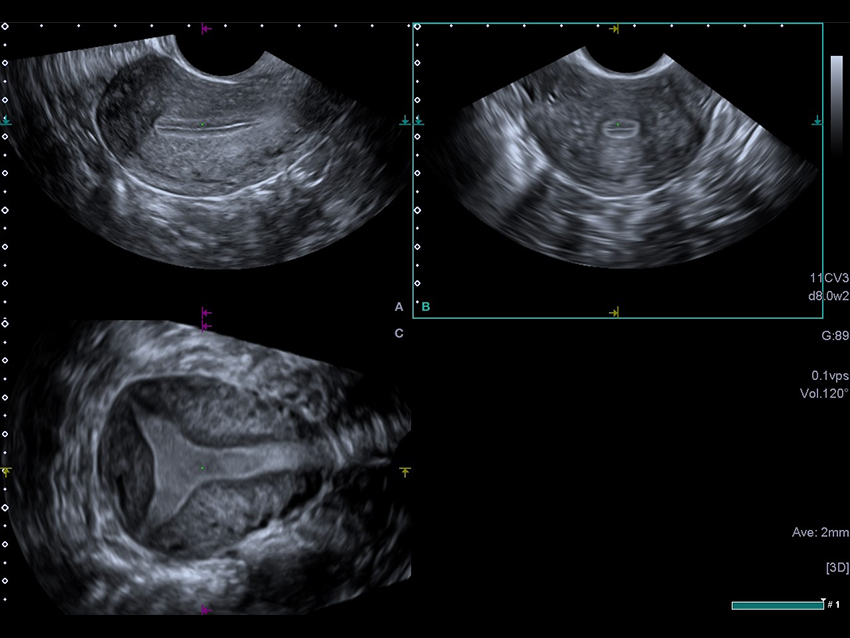

3D MPR зображення матки в трьох площинах з високою роздільною здатністю дозволяє клініцистам оцінити порожнину матки.